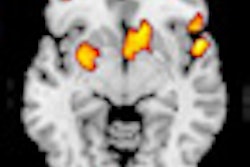

Key to management of diseases in the aging brain is understanding the structural visualized brain changes that occur in normal aging, which were presented by Dr. Frederik Barkhof, a professor of neuroradiology at the Free University of Amsterdam in the Netherlands. Widening in the Virchow-Robin spaces (VRS), as seen in MRI, is a normal aging phenomenon even in patients as young as 30, and of no pathological significance, he said. Some degree of atrophy of the medial temporal lobe was also sometimes visible.

Extreme widening in VRS was more difficult to determine. Patients often presented with headaches, but no discernible pathologies. It still might be a sign of normal aging, while homogenous dot-like structures of état Criblé was an abnormal finding indicating local atrophy often associated with diffuse white matter changes and always with a pathological finding.

"Normal aging is often defined as the absence of overt disease, but there are a lot of things happening below the threshold. There's a small group of people who, if you image them, have a healthy brain, but that's uncommon because most people with typical aging have some subclinical pathologies like white-matter lesions. The predictive value of these images is only partly known," Barkhof said. "Even if it's known, there are inferences at a group level, but on an individual level it is very difficult to make an exact determination of the impact down the line."

Determining whether patients will be able to live independently, and for how long, is crucial not only for the patients themselves, but also for their families. Unidentified white objects (UBOs) are probably a sign of mild hypoxia, and in a young subject should be reported as abnormal and lead to investigations. Once they start forming small bridges or become confluent, they should be considered abnormal, independent of age. Arterial spin labeling in subjects with extensive white-matter changes usually reveals poor perfusion of the tissue.

In one study, healthy subjects with severe confluent lesions (Fazekas grade 2 and 3) showed a 20% reduction in perfusion compared to patients with milder lesions. A LADIS study imaging patients with mild, moderate, or severe confluence showed that 60% of 639 subjects with severe white-matter lesions were unable to live independently at home after three years or had died, even though they were doing well at the time of scanning. The results indicate that healthy subjects with severe white-matter lesions have a poor prognosis, Barkhof pointed out.

Premature aging can be predicted through imaging markers, highlighting confluent white-matter lesions, silent infarcts, cerebral microbleeds, medial temporal atrophy, and amyloid markers.

ECR delegates heard how patients with Alzheimer's disease (AD) have increased amyloid binding, but presence of amyloid didn't necessarily mean a patient would develop AD or predict when they would develop it. However, functional biomarkers could show whether amyloid was interfering with brain function and also aid in predicting premature aging. New PET tracers could rule out AD in favor of other diseases.

"MR or CT should be used to work up suspected dementia and rule out treatable disorders, or suggest a specific diagnosis. If scans are negative, PET/SPECT should be used," he said. "PET/MRI can also help to diagnose early dementia, even short of established therapy."